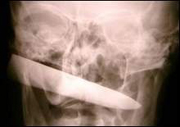

У везучего поляка в голове нашли 12-сантиметровый нож

61-летнему жителю Польши крупно повезло – после того, как 12-сантиметровое лезвие ножа вошло ему в голову, он выжил. Кроме того, поляк даже не подозревал, что у него в голове находится инородный предмет.

Бывший школьный учитель Леонард Воронович из города Войновице узнал о том, что в его голове находится нож совершенно случайно. С жалобами на головную боль после неудачного падения на кухне он обратился к врачам. Те, желая проверить, не ушиб ли пациент челюсть, сделали рентген.

Однако, каково же было удивление медиков, когда вместо перелома или хотя бы трещины кости они обнаружили в голове у Леонарда нож.

Лезвие вошло аккурат под правым ухом пациента при этом не задев ни одного основного кровеносного сосуда или нерва. Кроме того, Леонард не испытывал с 12-сантиметровым лезвием в голове значительных неудобств – лишь немного побаливала пострадавшая часть тела.

Врачи в госпитале города Войновице не могли поверить свои глазам, обнаружив нож в голове Леонарда. Пострадавшего отправили в больницу города Бясток, где ему была сделана операция. Примечательно, что она длилась всего несколько минут.

Доктор Марек Роговски из госпиталя города Бясток назвал случай Леонарда "беспрецедентным".